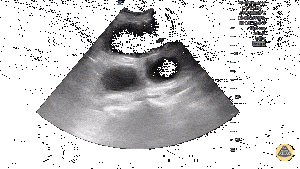

US showing dilated loops of bowel, bidirectional peristalsis, "keyboard" sign, and free fluid[5]

- SBO criteria include:

- Dilated loops of bowel >2.5cm

- Bidirectional peristalsis

- Additional findings include:

- "Keyboard" sign which are finger-like projections that represent plicae circulares

- Bowel wall edema

- Intraabdominal free fluid

- Sonographic transition point